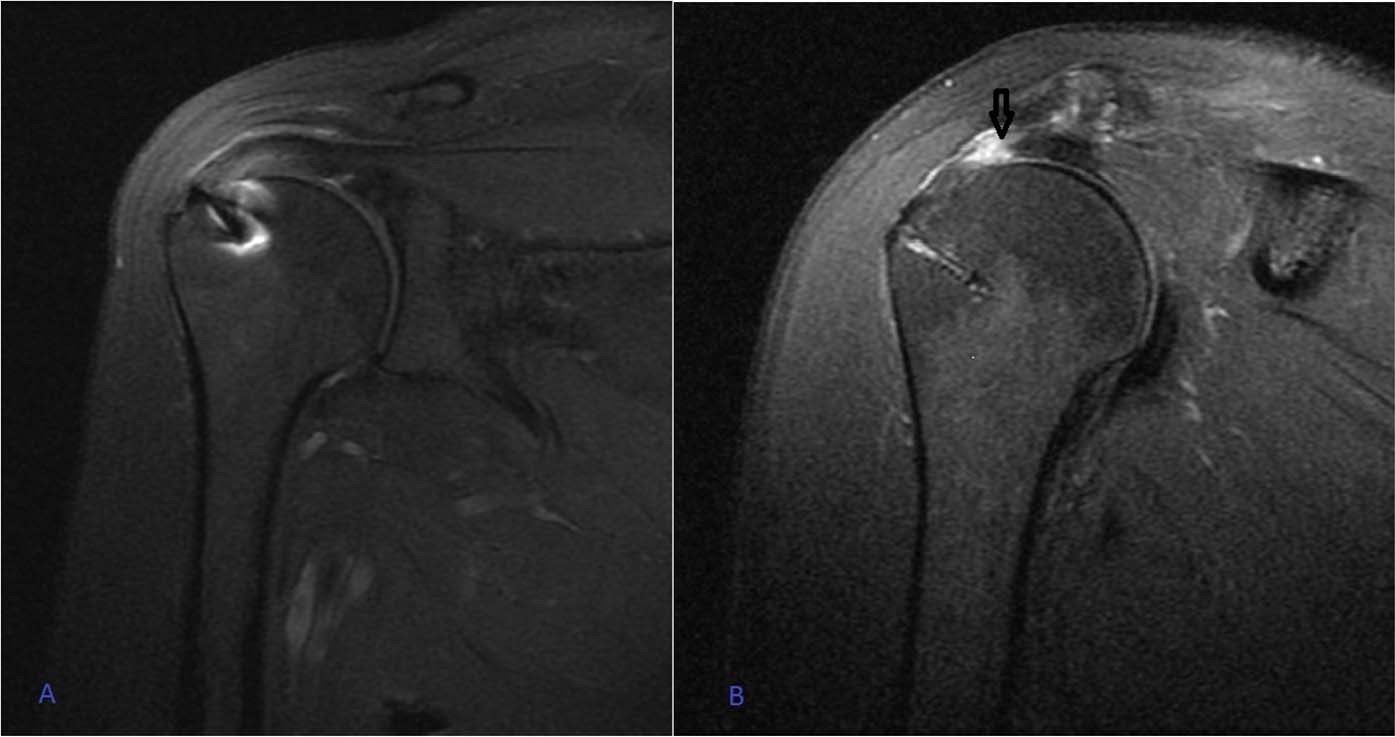

Figure 2

(A) Intact repair at the first year shoulder coronal MRI sequence in a group 2 patient. (B) Retear at the first year shoulder coronal MRI sequence in a group 3 patient. Black arrow shows Sugaya type 5 retear.